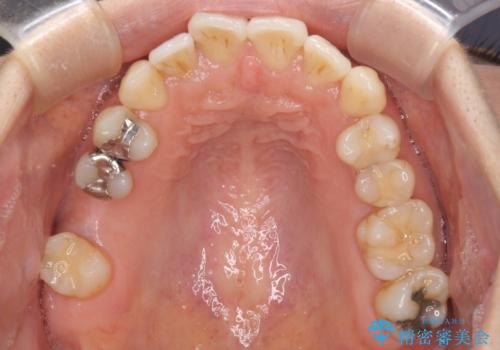

- 上下奥歯の欠損を気にして来院された患者様です。

以前矯正した後戻りにより前歯に叢生が認められたため、矯正治療の提案をしたところ、補綴治療と合わせて矯正治療を行うこととしました。

下顎欠損部はインプラントにて、上顎中間欠損部はブリッジによる補綴治療を行い、他にも気になっている銀歯をセラミックインレーやゴールドインレーにて修復治療を行うこととしました。

後戻りの程度は軽度であったため、インビザライン・ライトを用いて歯列を整えました。

再度後戻りするリスクを最小限に食い止めるため、下顎前歯の舌側を細いワイヤーで固定しました。